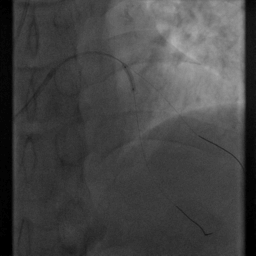

4.追加3500U肝素,择6F EBU3.5指引导管送至左冠口,Runthrough导丝送至LAD远段,择sion导丝送至D1远段

5.择2.5*15mm球囊送至LAD病变处,以12atm*8s扩张

6.择resolute3.0*18mm支架送至LAD中段病变处,以12atm*8s释放支架。

重复造影:前向血流TIMI Ⅲ级,支架近段贴壁欠佳,无夹层、残余狭窄等,D1开口狭窄较先有所加重